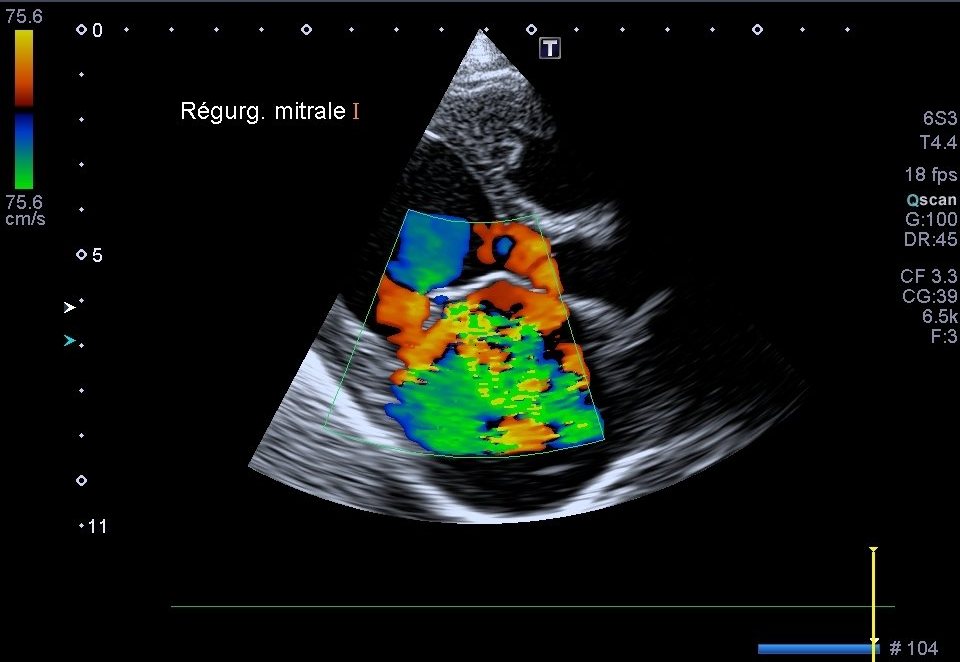

Échographie Cardiaque

L’échocardiographie est utilisée comme son nom l'indique dans l’exploration spécifique du coeur. Elle permet donc particulièrement le suivi des maladies cardiaques.

Nous pouvons mesurer précisément les cavités du coeur, observer la contraction du muscle cardiaque et ainsi visualiser la circulation du sang. Elle peut être complétée par une mesure de la tension artérielle et la réalisation d’un électrocardiogramme, conjointement à d’autres examens comme la radiographie thoracique.

Une prise en charge médicale la plus précise possible est alors proposée. Avec une telle technologie alliée à l'expertise de vos vétérinaires qui se forment en continu, une maladie cardiaque ou cardiopathie peut être détectée très tôt.